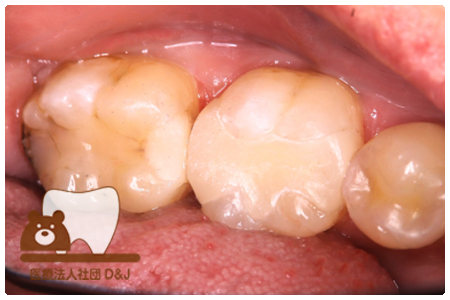

症例8フルジルコニアクラウン

治療前

治療中

治療後

29歳 女性

- 治療内容

- 銀歯からフルジルコニアクラウンへの修復

- 治療期間

- 根の治療含め3か月

- 費用

- 自費

フルジルコニアクラウン:77,000円(税込)

- その他の治療の費用は含まれておりません。

- リスク・副作用

- 強い衝撃が加わると欠けたり割れたりする可能性があります。また、噛み合わせの状態によっては脱離や周囲の歯への影響が出ることもあります。